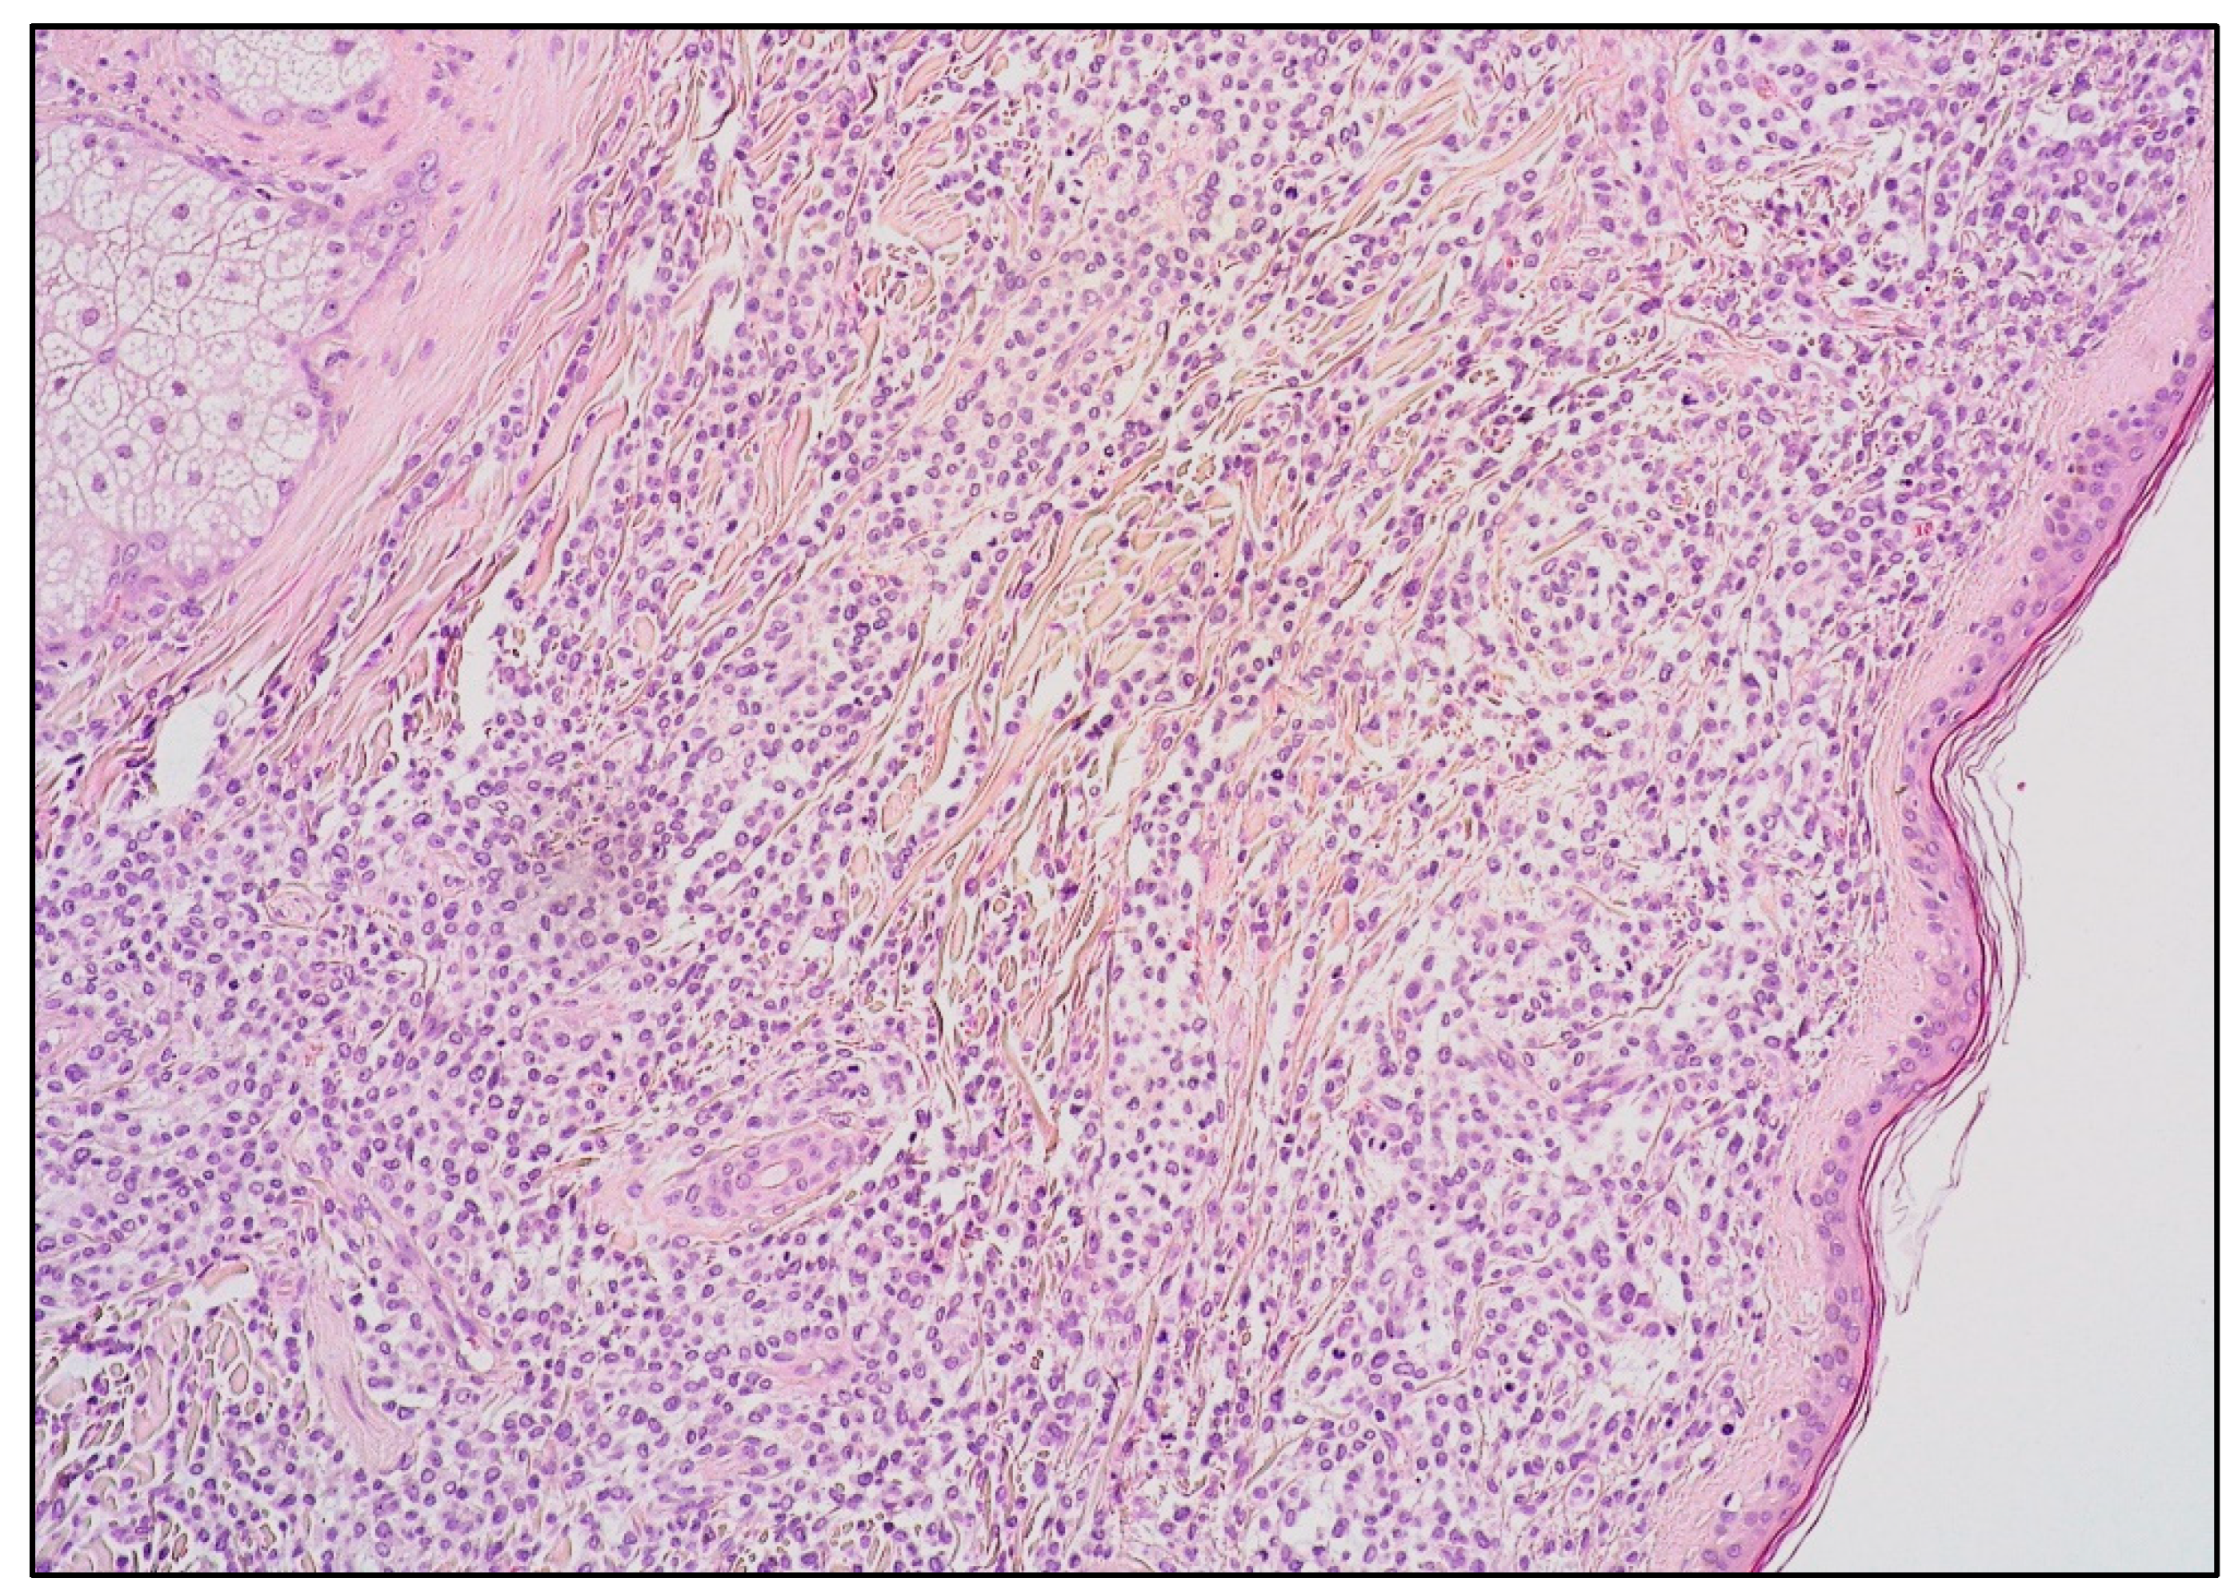

7. Histology and Immunophenotypic Features of B-LBL and T-LBL

8. LBL and Skin Involvement